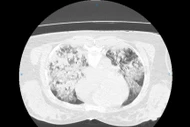

Bệnh nhân mắc 3 ung thư tiêu hóa hiếm gặp được cứu sống sau phẫu thuật phức tạp kéo dài hơn 13 tiếng, với sự phối hợp nhiều chuyên khoa.